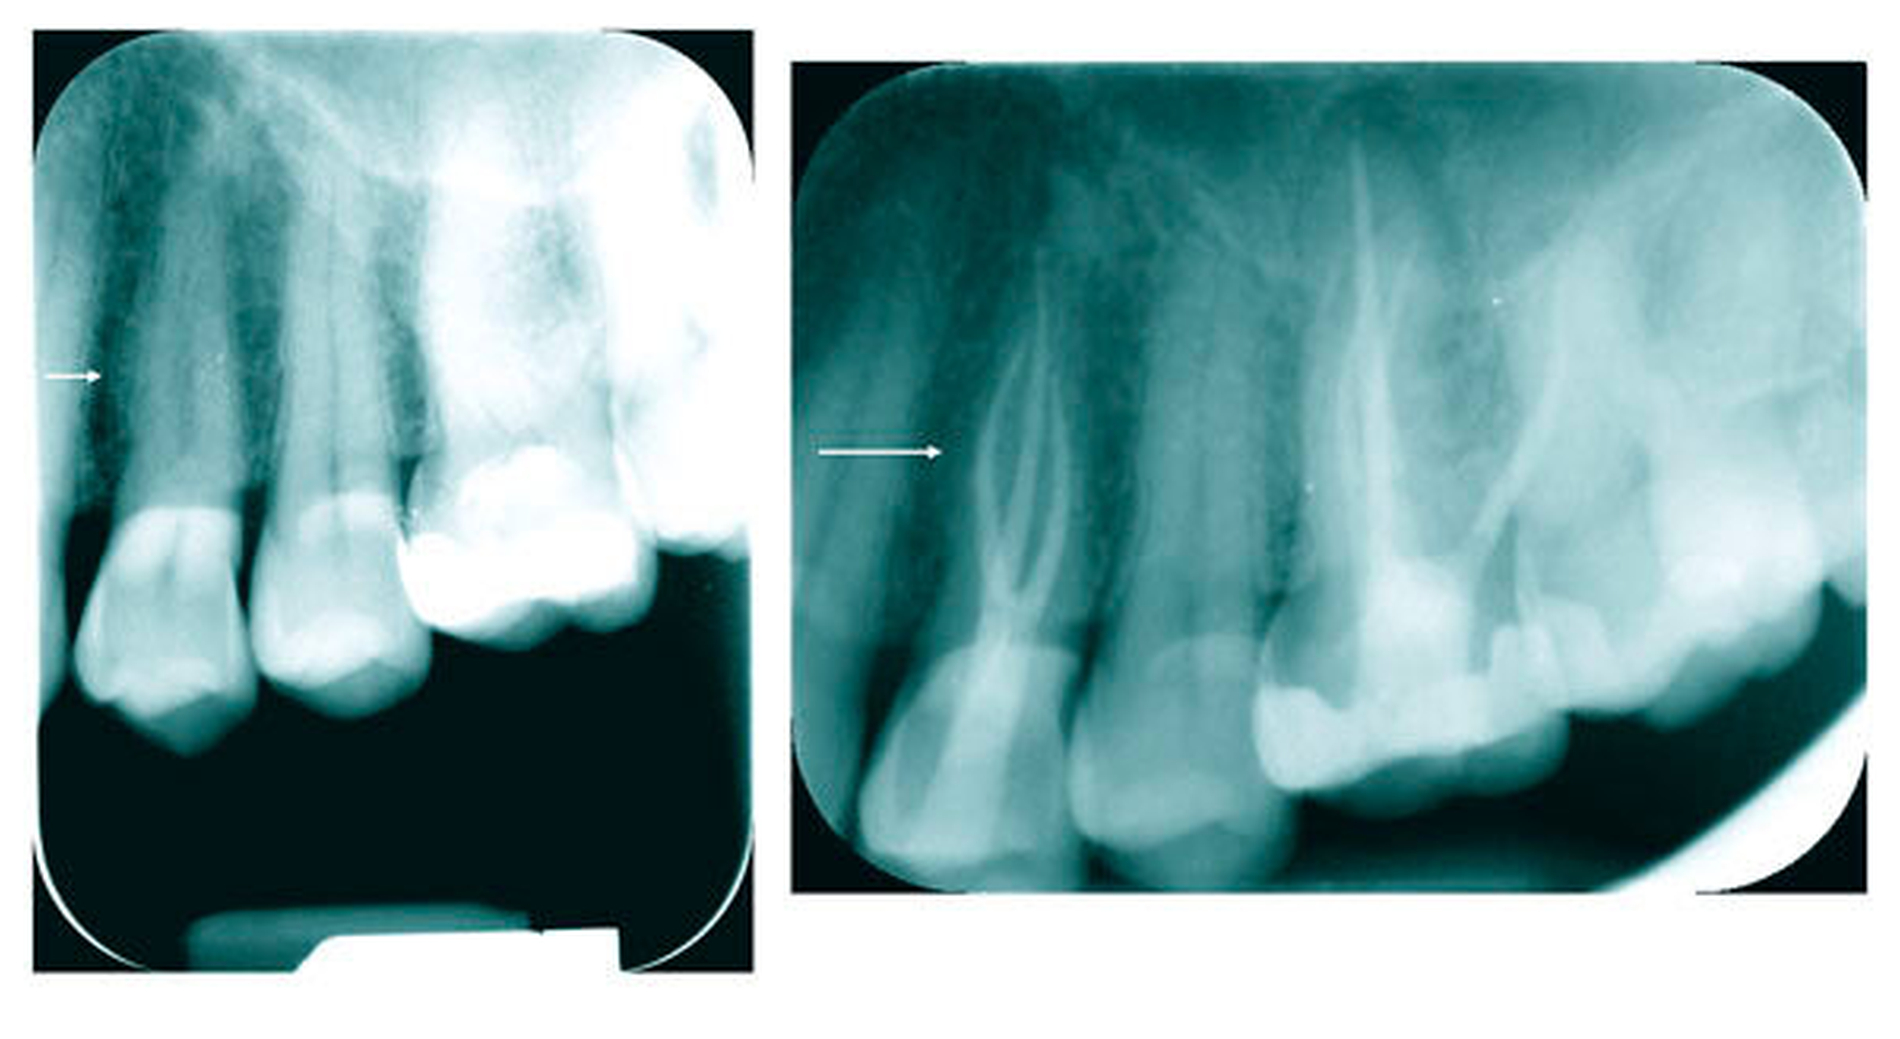

Drei mögliche Hinweise können bei der Diagnostik eines dreikanaligen Prämolaren hilfreich sein. Der erste Hinweis ist eine nicht klar abzugrenzende Wurzelkontur in der diagnostischen Röntgenaufnahme. Dreikanalige obere Prämolaren zeigen im klassischen Röntgenbild im koronalen bis mittleren Wurzeldrittel eine oft bauchige Struktur. Diese korrespondiert in der Regel mit der Stelle apikal der Aufteilung in zwei bukkale Kanäle (Abbildung 8). Klinisch kann dann in den meisten Fällen bei Sondierung bukkal eine deutliche Einziehung unterhalb der Schmelz-Zement-Grenze mit der Sonde ertastet werden, dies ist der zweite Hinweis (Abbildung 9). Der dritte Hinweis zeigt sich nach Trepanation und Darstellung des Kavumbodens und des vermeintlichen bukkalen Kanaleingangs. Dieser wird häufig nach hinreichender Darstellung in mesiodistaler Richtung oval und gibt dann die Sicht auf die beiden eigentlichen Kanäle frei (Abbildungen 10 und 11).